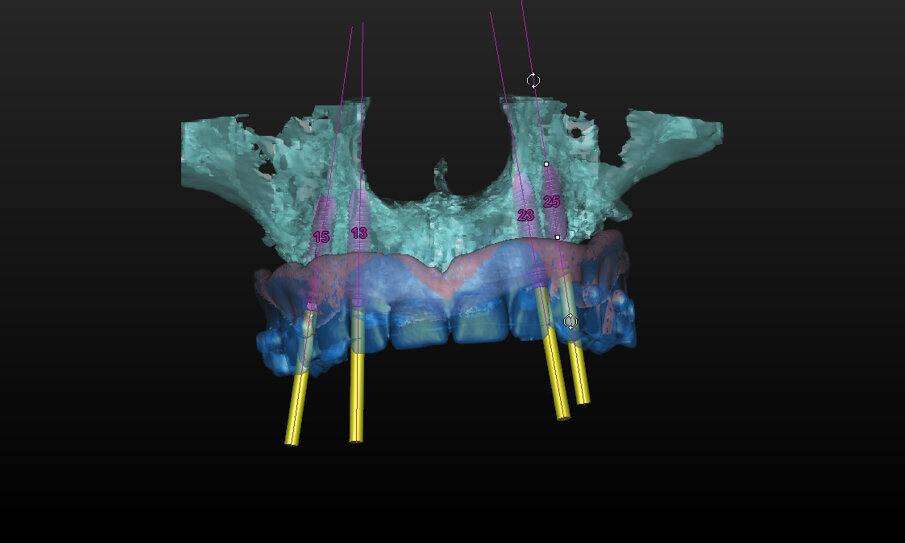

The dual-scan protocol was used to visualise bone, soft tissue thickness and denture position in the Simplant software (Dentsply Sirona). Four DS PrimeTaper EV 3.6 mm diameter implants were planned according to the position of the patient’s denture, and four Multibase abutments (Dentsply Sirona) were visualised accordingly (Fig. 3).

Fig. 3: Implant treatment planning in Simplant using the dual-scan protocol to visualise tooth position as well as abutment position. Four DS PrimeTaper implants were planned for immediate restoration.